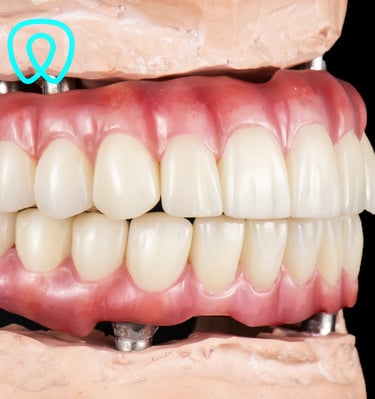

Contamos con todas las especialidades dentales: ortodoncia, implantes, cirugía, endodoncia, periodoncia, odontopediatría, odontología cosmética, prótesis dental.

Servicios Dentales

Atención integral en odontología para todas las edades y especialidades con enfoque en la prevención.